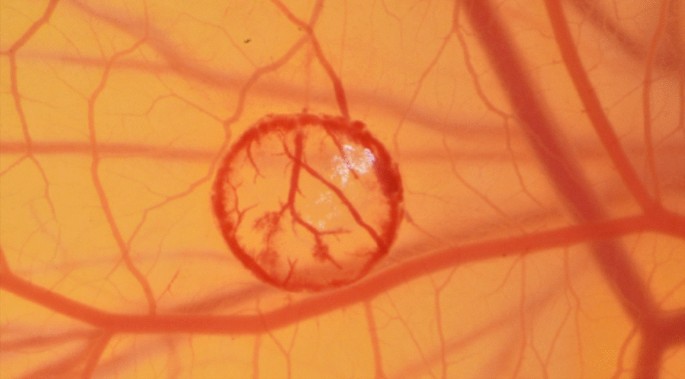

On the 8th day of embryonic development, a burn wound was induced on the CAM surface of all embryos using a forceps with a rounded tip, preheated to a temperature of 100 °C. A circular burn wound with a diameter of 10 mm2 was created by gently pressing the instrument on the surface of the CAM for one second. To ensure experiment reproducibility, precise temperature measurements were obtained using an infrared thermometer. The placement of the burn wounds was carefully chosen in areas of interest between major blood vessels, to visualize the ingrowth of capillaries while minimizing the risk of lethal injuries. Following the induction of the burn wounds, the CAMs were numbered and randomly assigned to either a control or intervention group using specialized randomization software. Figure 4 shows the surface of the chorioallantoic membrane right after placing a burn wound.

To analyze vessel sprouting, the burn was assumed to be approximately circular in this study. First, a circle with a distance of 1 mm to the outer edge of the wound was drawn. We maintained a consistent 1 mm distance from the outer edge of the burn wound for vessel ingrowth analysis, resulting in a proportionally shrinking region of interest during the wound healing process.

Afterwards, intersecting vessels were marked and manually counted. Figure 7 shows the manual count of ingrowing vessels.